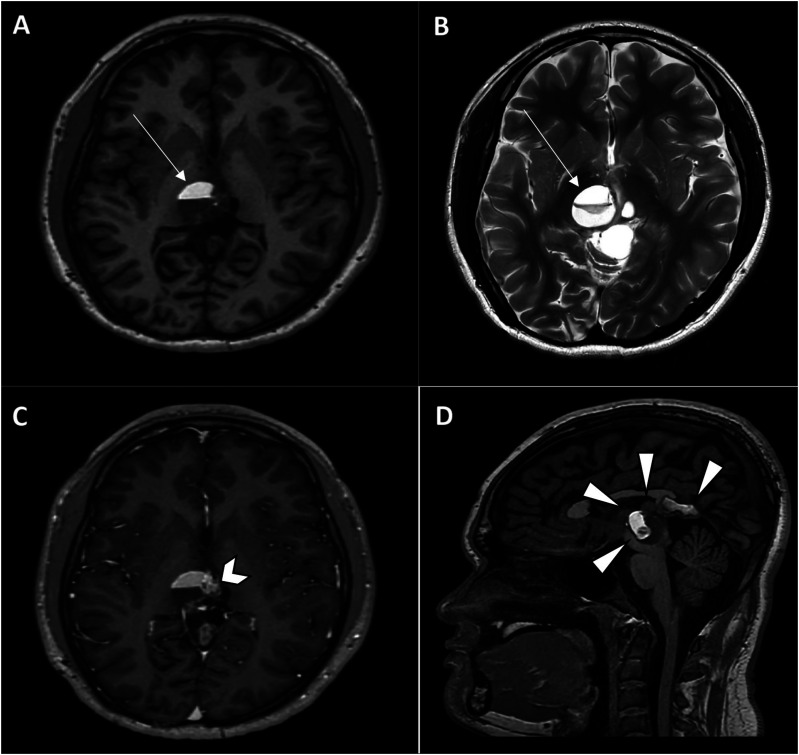

Teratomas are a common type of germ cell tumours which may be benign or malignant. Benign mature teratomas are the most frequent subtype and typically show intralesional fat and calcifications within a cystic mass. Immature/malignant teratomas are usually larger with irregular solid components, coarse calcifications, small amounts of fat, and with or without necrosis or haemorrhage. Teratomas can manifest in various anatomical locations, particularly in the sacrococcygeal, gonadal, mediastinal, retroperitoneal, and intracranial regions. This article explores the imaging characteristics and diverse locations of teratomas as well as discusses about possible differential diagnoses to facilitate early detection and ensure prompt treatment.

Abstract Image